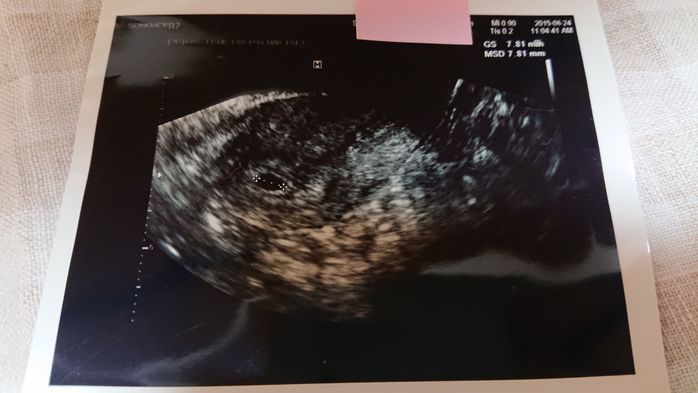

《妊娠5週目のエコー写真》

初めてのエコー検査からちょうど1週間後、赤ちゃんがおなかにやってきてくれたか、再度、確認する日がやってきました。まだ、赤ちゃんの姿は見えないけれど、胎嚢という赤ちゃんが育つためのお部屋が出来ているのを確認できました。胎嚢はエコー写真の黒丸部分です。私自身、「自分の体は妊娠できるのか」と長年不安だったので、前回は何も写っていなかったエコー写真を見たときは不安でしたが、今回は、くっきりと赤ちゃんのお部屋である胎嚢を見つけることができ、感動しました。